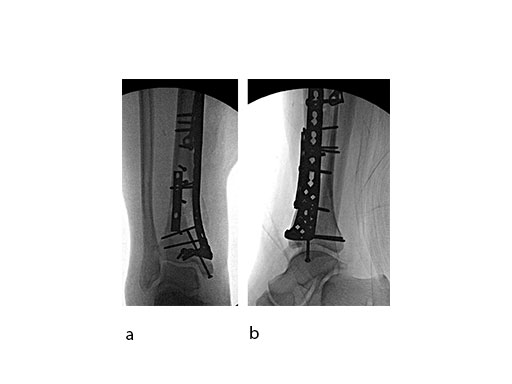

Push technique was required to achieve fibular reduction, and the syndesmosis was reduced and clamped with periarticular clamps (Fig 11). Postoperative x-rays at 4 weeks demonstrated good maintenance of reduction (Fig 12).